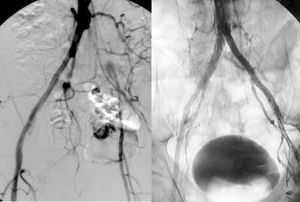

When the obstruction extends to the infragenicular popliteal artery and the distal vessels, revascularization is carried out with bypass surgery whose distal anastomosis is done in the distal vessel with the best state to ensure direct perfusion to the foot (Figure 8). In this case we refer to femorodistal, popliteodistal, or tibiotibial revascularization surgery, depending on the site of the proximal anastomosis. In general, these bypass operations are associated with similar rates of permeability to those obtained with bypass to the popliteal artery, provided that autologous material is used, but much worse when a prosthesis is used. Nevertheless, the rates of limb salvation surpass 70% at 5 years.

Figure 8. Femoroperoneal venous bypass surgery. Control arteriography.